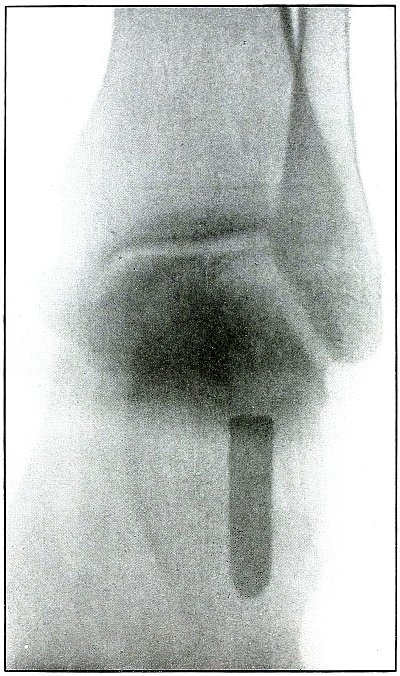

Plate 66.

_

[Pg 143]

Rifle—Plate 66.

LOWER EXTREMITY.